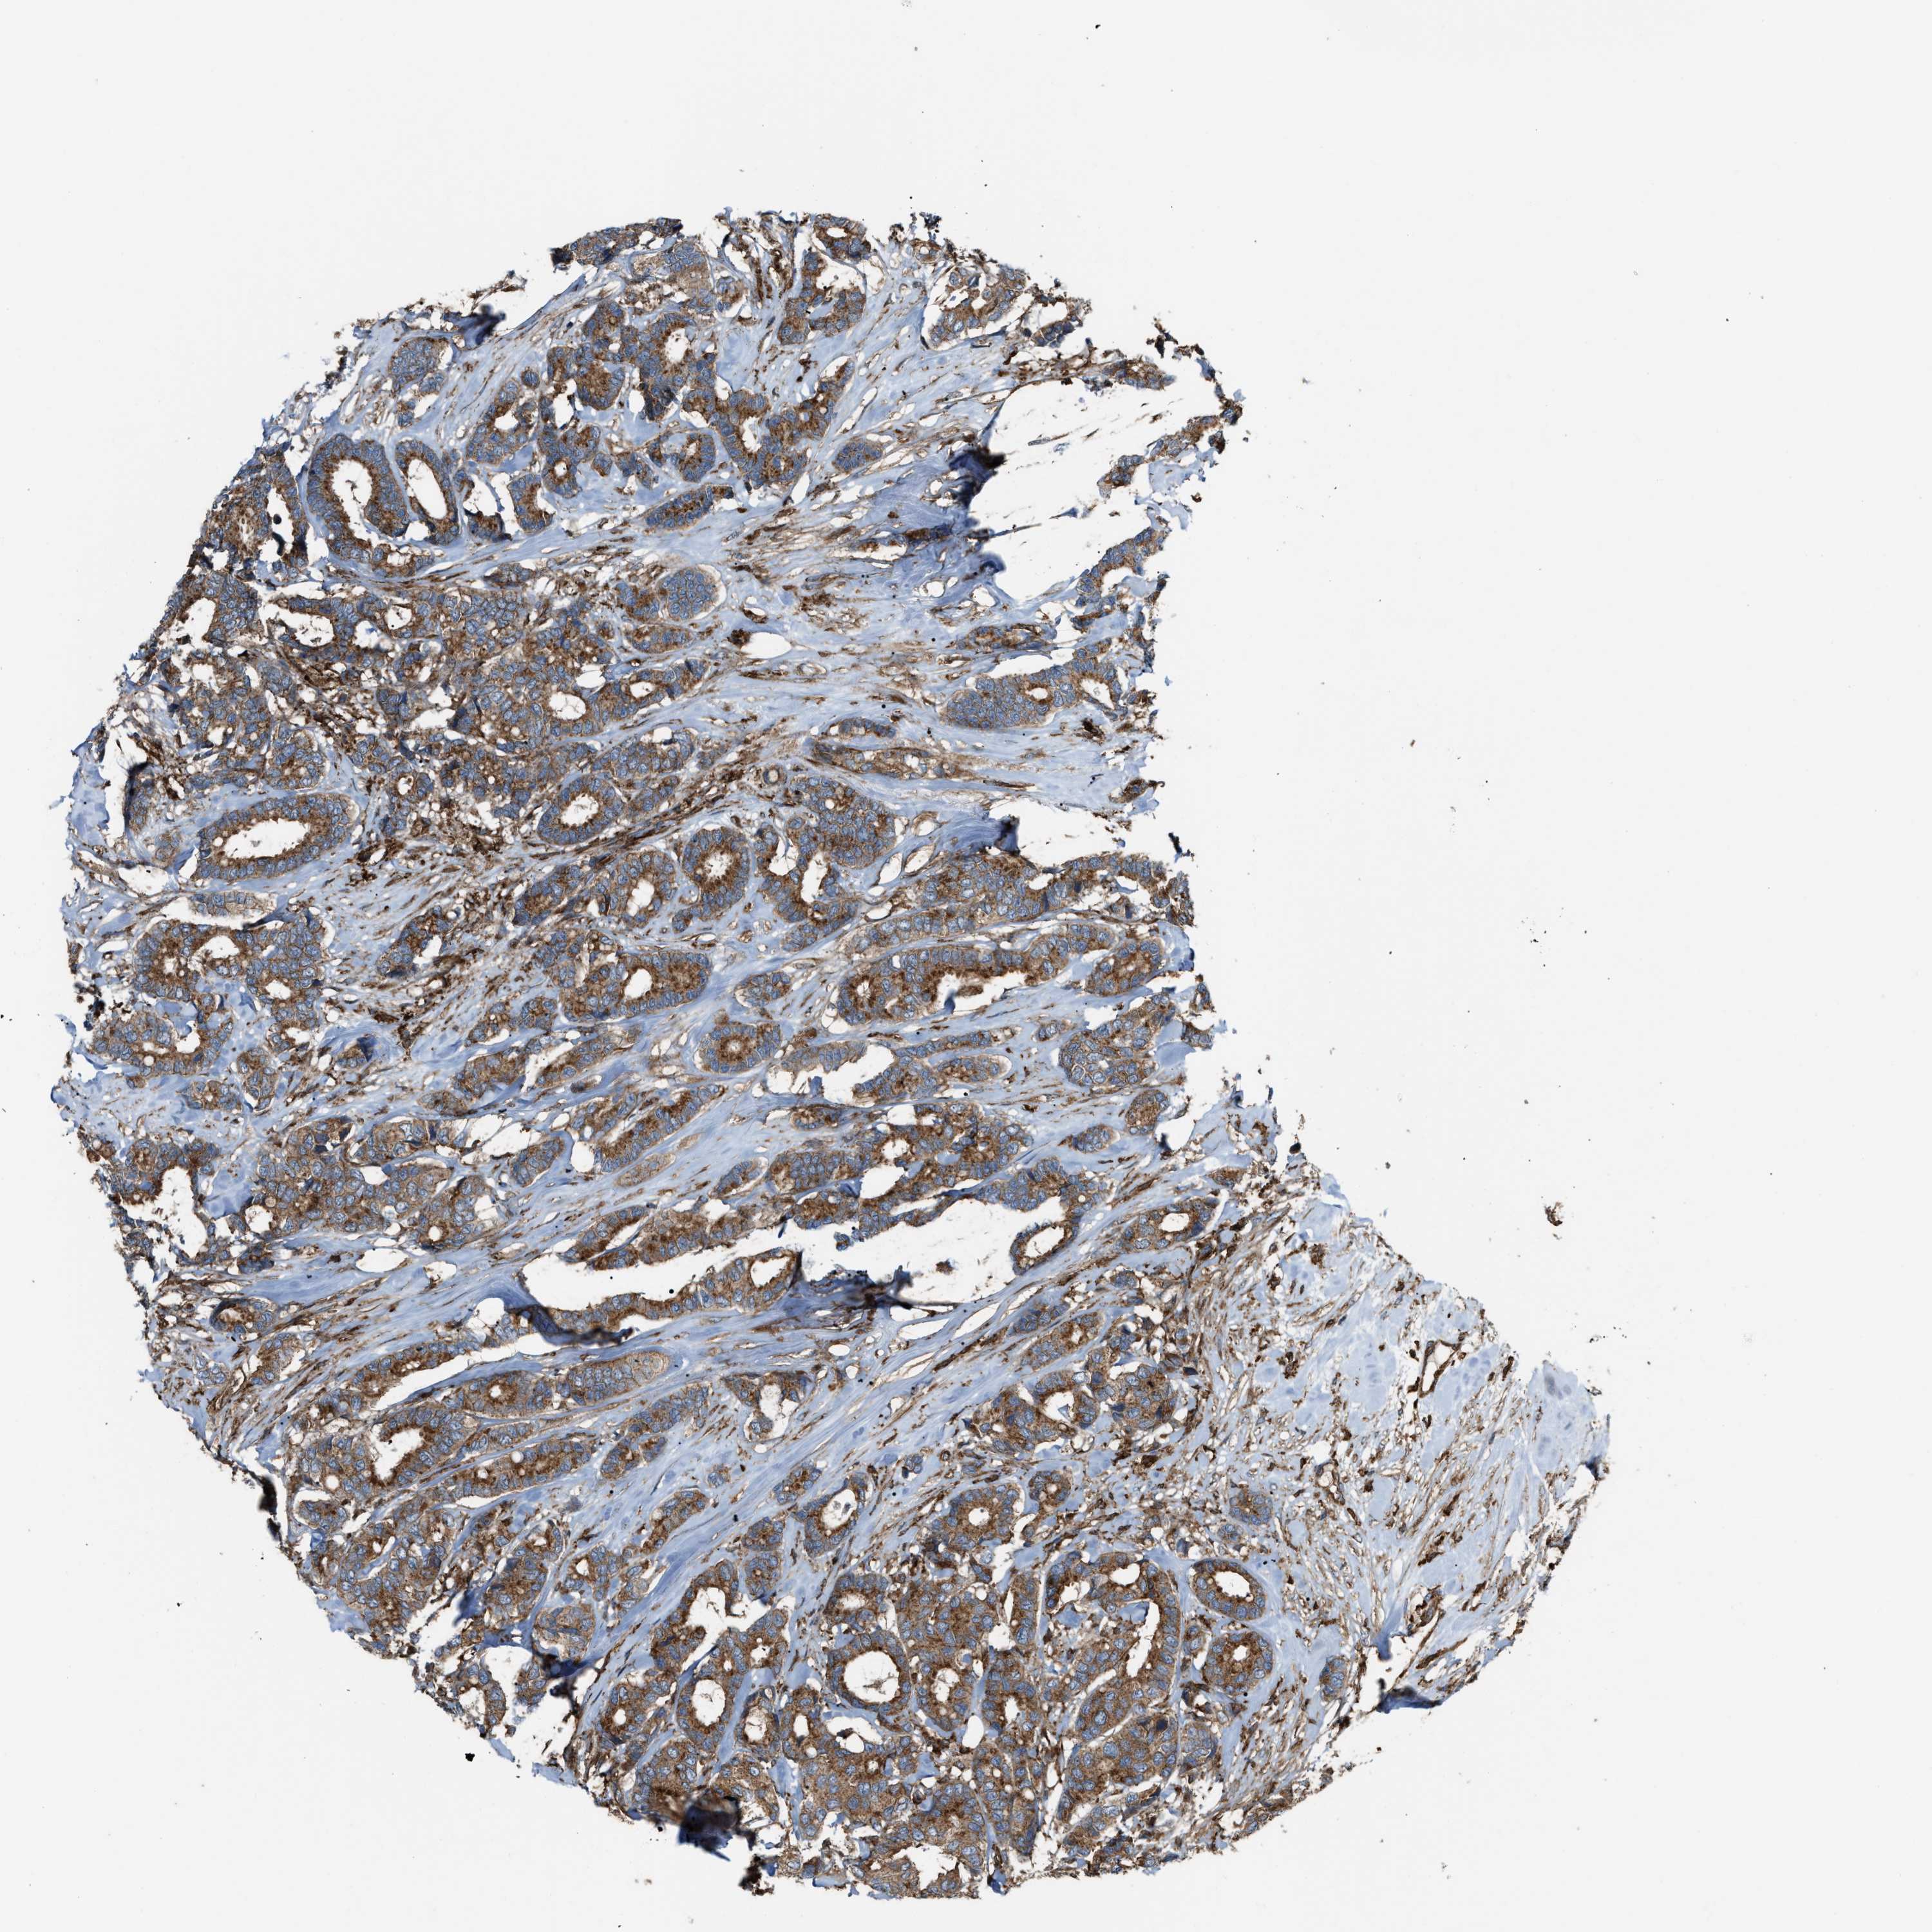

CANCER BREAST CANCER Show tissue menu

BRCA TCGA BRCA VALIDATION PROTEIN EXPRESSION